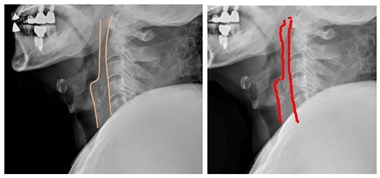

실제 치과 보철치료를 받은 외상환자의 경추 X-ray 영상을 영상의학과 의사가 판독(사진 좌측)한 결과와 AI가 판독(사진 우측)한 결과를 비교했을 때 큰 차이는 나타나지 않았다.

엑스레이를 판독할 때 척추 앞 공간을 보기 위해 척추 앞 공간선을 그리게 되는데 AI 역시 의사가 그린 공간선과 같은 모양을 그렸다.